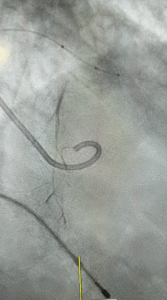

Como é feito o procedimento por cateter?

O cateter oclui os vasos sanguíneos que nutrem o excesso de músculo responsável pelo problema.

Sem nutrição, o excesso de músculo definha e não mais obstrui a saída do coração.

A substância que oclui a artéria nutridora do excesso de músculo é um copolímero, ou álcool.

Copolímero parece ser mais seguro que o álcool.

O médico ecocardiografista participa do procedimento.

Ele oferece informações úteis à orientação e segurança do procedimento.